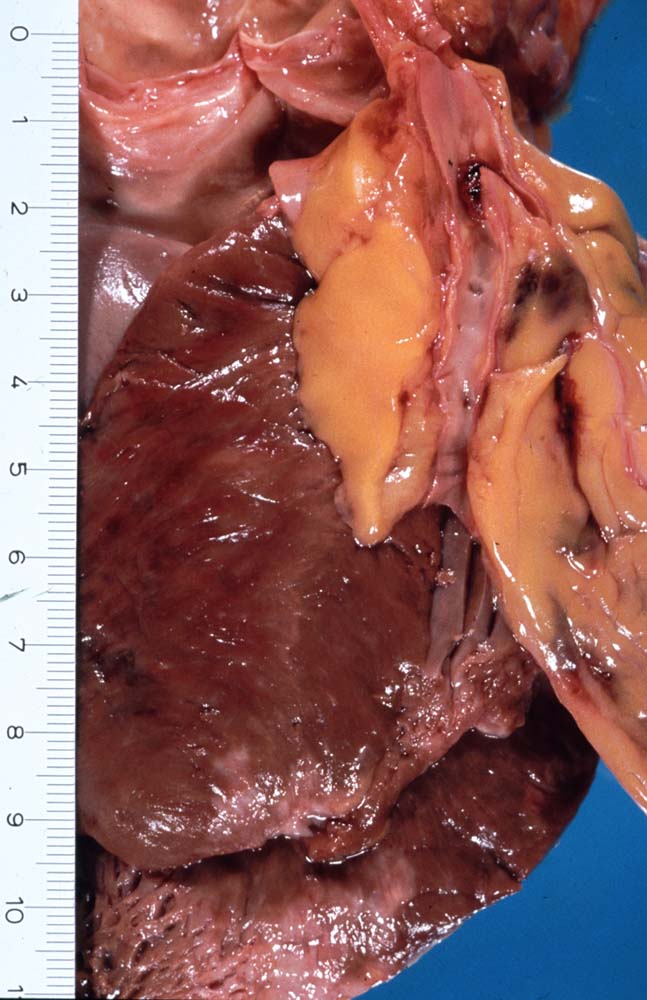

PathoPic ID 8854 - Koronarthrombose

Koronarthrombose

vaskulär / Durchblutungsstörung

Arteria coronaris

Kardiovaskuläres System

An der Bifurkation des RIVA/Ramus diagonalis ist das Lumen des RIVA

thrombosiert. Auf der Schnittfläche der Vorderwand ist eine Infarktnarbe und eine fleckige Verfärbung des Myokards (akuter Myokardinfarkt) erkennbar.